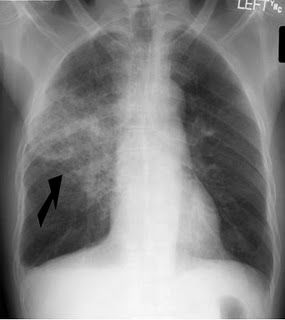

1. RX-Tórax